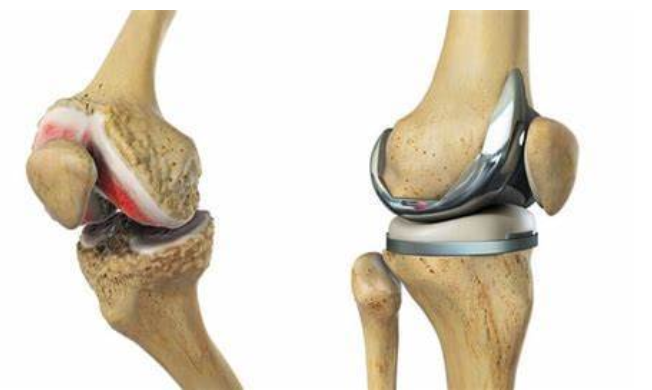

膝关节骨性关节炎

带你正确认识膝骨关节炎

第一张图片是前内侧骨关节炎骨磨骨阶段,如果膝关节疼痛,拍x线 - 抖音